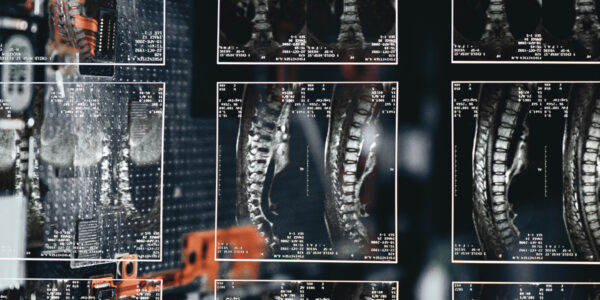

Automatizált gerinc MR leletező és vizualizált leletértelmező rendszer

Automatizált gerinc MR leletező és vizualizált leletértelmező rendszert fejlesztettek

Az AUTORAD projekt keretében többek között az orvos-beteg kommunikáció eredményességének javítása céljából egy vizualizált gerinc MR lelet megjelenítő rendszer, valamint egy intelligens leletkezelő...